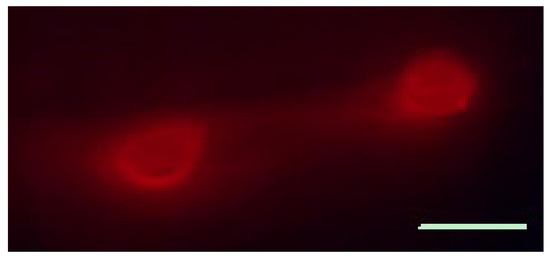

3.6. Calcium Imaging of SGC Responses to ATP